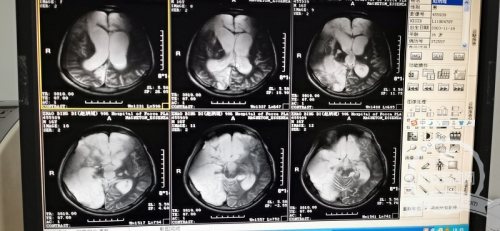

情况比想象的更糟糕,这是接诊的神经外科主任赵永博的第一反应。孩子的整个表现是一个去皮层强直的状态,四肢僵硬的让人担心一不谨慎会掰折,体温随时会因为肌肉强直收缩超过40℃。看着右侧大脑半球大面积梗塞的片子,相比之前治好过的不少意识障碍患者,这个患儿的治疗难度更大。